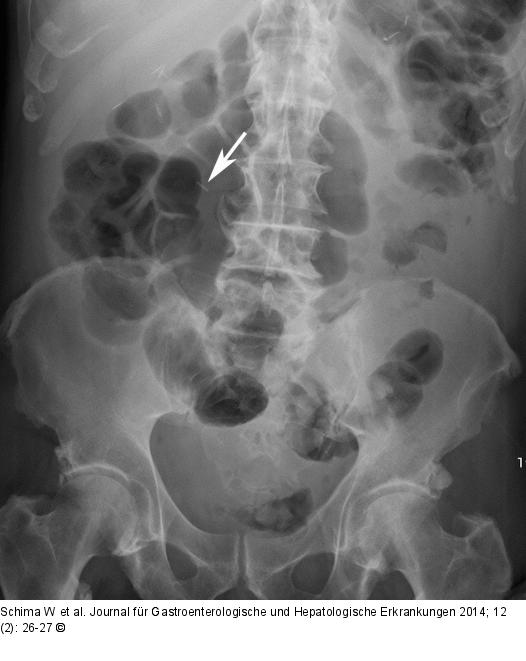

Abbildung 4: Abdomenübersicht In der Abdomenübersichtsaufnahme nach der ERCP erkennt man den nach distal wandernden Clip, vermutlich im C. sigmoideum (Pfeil). |

In der Abdomenübersichtsaufnahme nach der ERCP erkennt man den nach distal wandernden Clip, vermutlich im C. sigmoideum (Pfeil). |